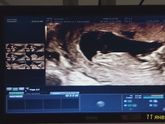

Восьмой месяц. 32 недели. Пдр 30 июля. Но открытие уже было. Хочу хоть до 34 доходить. Почему то решила для себя что это уже безопасный срок. После ухода в декрет чувствую себя хорошо. Отоспалась и отъелась...долбанная работа-и отслойка и обострение … Читать далее